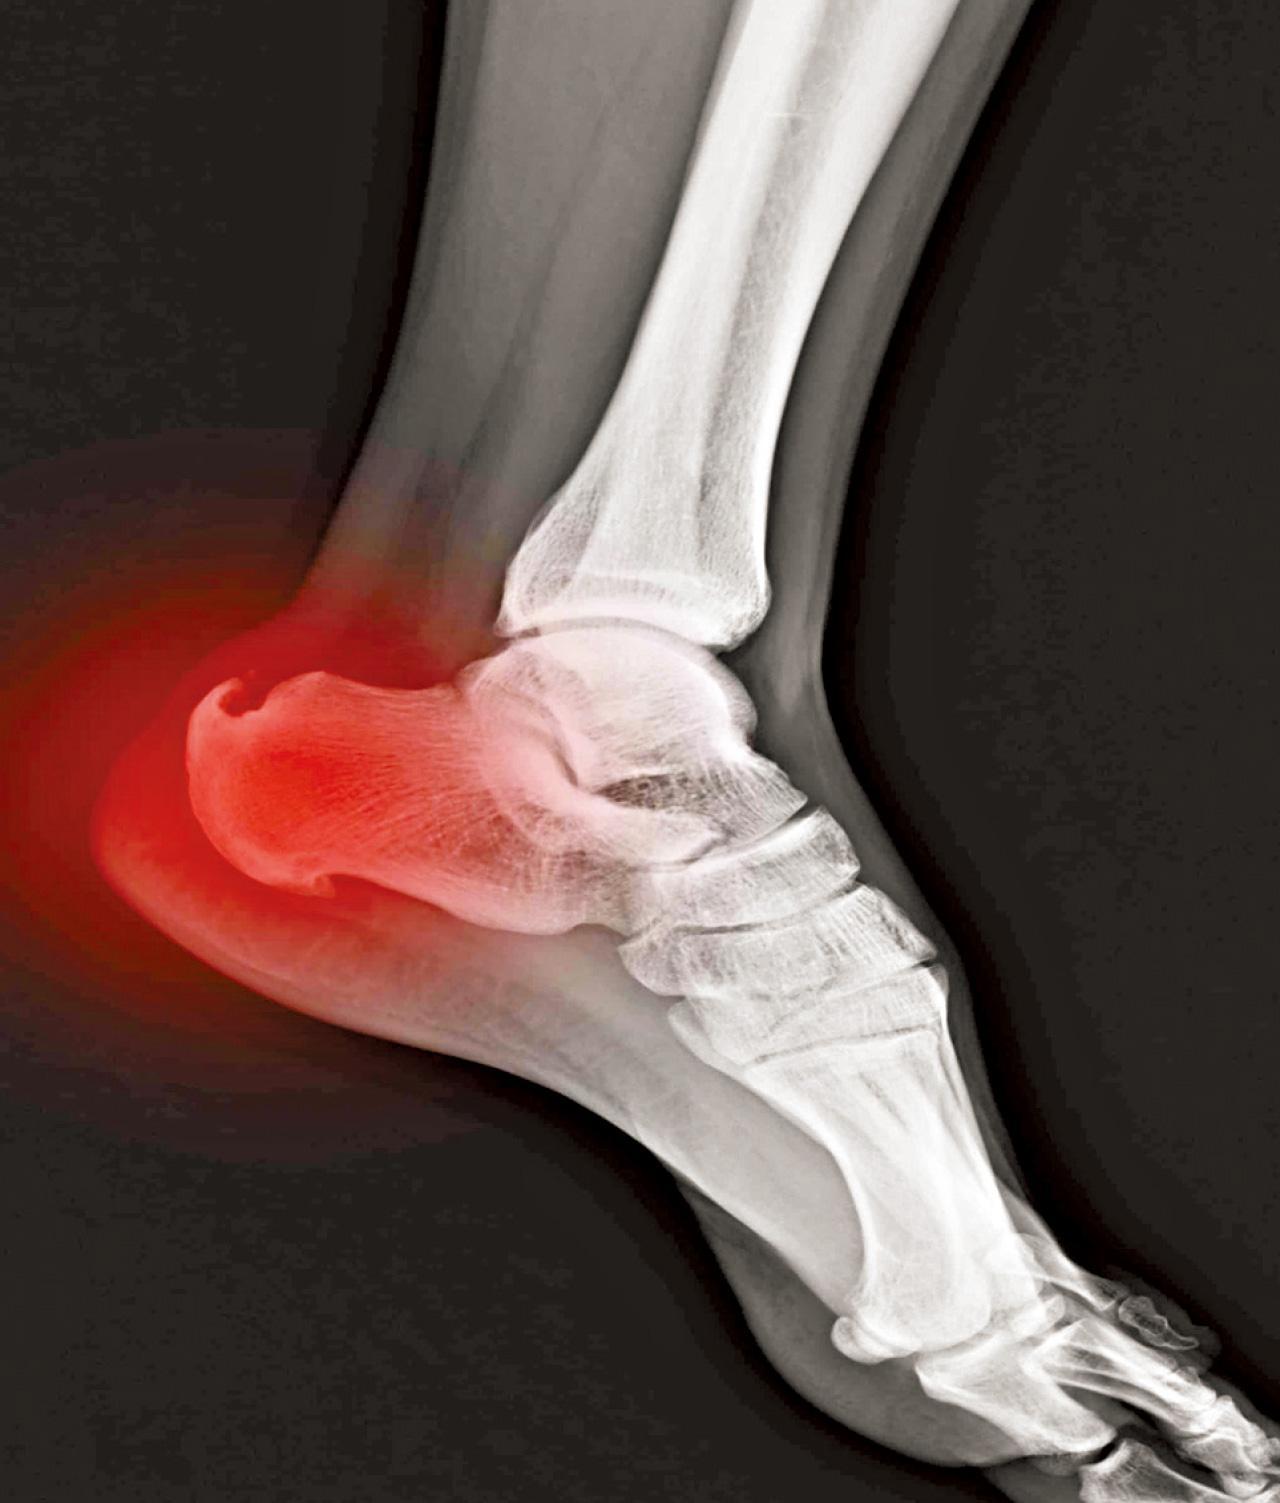

為甚麼會有骨刺呢?其實透過觸摸一下雙腳腳眼可略知一二,身體上一些較突出的位置都是由肌肉或韌帶反覆拉扯而形成。而骨刺的形成一樣是因為軟組織經過反覆用力或肌肉繃緊而造成。所以,其實骨刺是伴隨著大量軟組織繃緊及勞損問題。